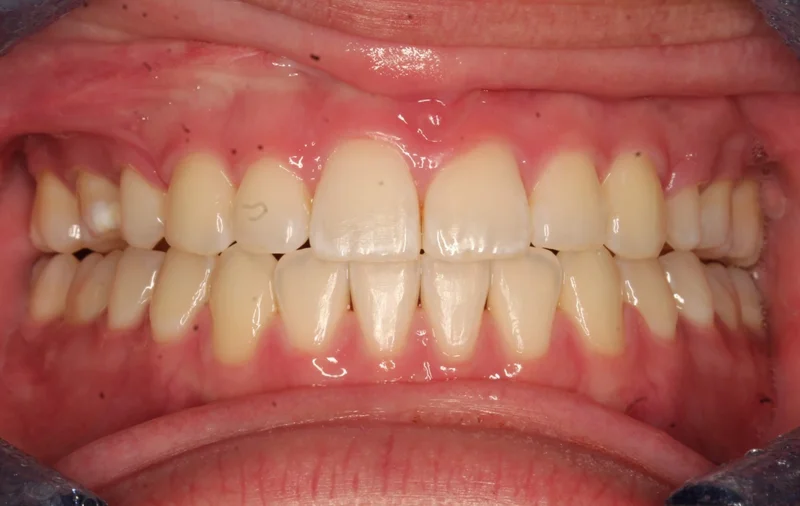

Case #90850 | 18 - 29 | Female

This young woman in Las Vegas came to us with a severe class III malocclusion (underbite) and the only option to correct her bite was with extractions on the upper arch and orthognathic surgery with an oral surgeon. She needed to have two teeth extracted first on the upper arch as part of the presurgical orthodontics to correct the severe proclination of the upper incisors. We first decompensated for this proclination by uprighting the upper incisors and closing the extraction space, which actually makes the overjet worse prior to surgery. She then had a double jaw surgery, including a Le Fort maxillary advancement as well as a mandibular setback. After about 6 weeks of post-surgical healing, she resumed orthodontic treatment to finish up. Her total treatment time was 27 months.

Center - After Treatment

After